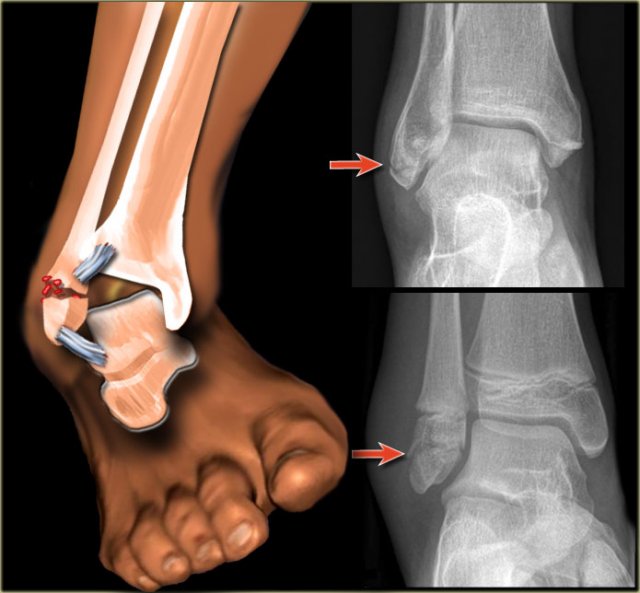

PE stage 1 PE stage 1

• Re-examination

On the ankle films there was no sign of an oblique fracture of the lateral malleolus, so we can exclude a Weber B fracture.

There is still the possibility of a Weber C fracture stage 4, i.e. medial rupture or avulsion, high fibular fracture and finally a posterior malleolus fracture.

At reexamination you notice the subtle avulsion of the medial malleolus (red arrow), which is stage 1.

Notice also the soft tissue swelling on the medial side (blue arrow)